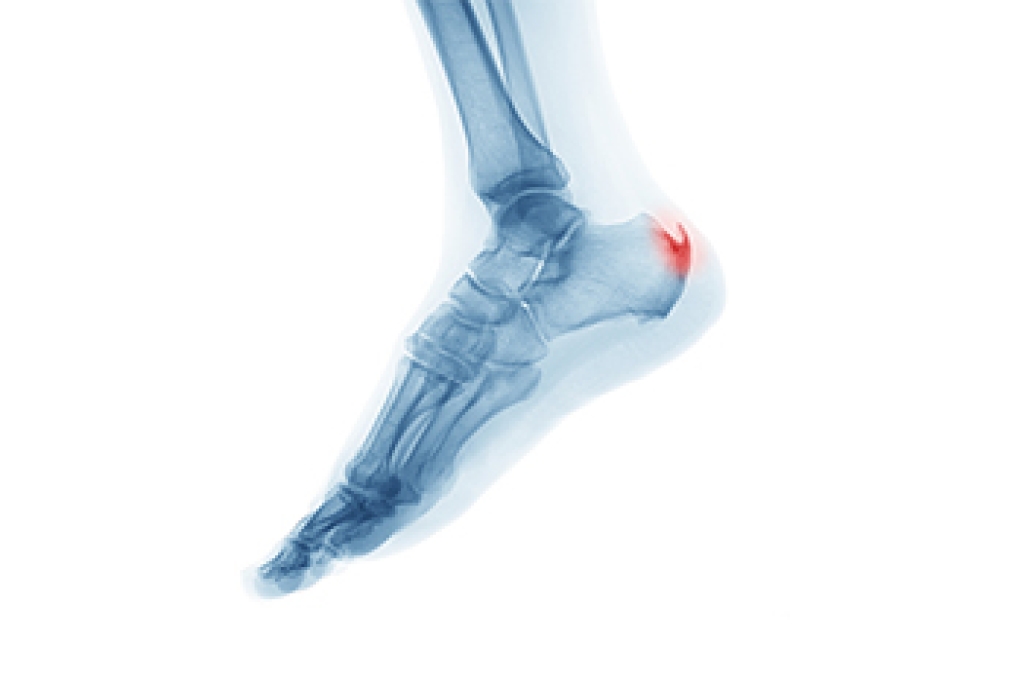

Heel pain is often associated with plantar fasciitis. The plantar fascia is a band of tissues that extends along the bottom of the foot. A rip or tear in this ligament can cause inflammation of the tissue.

Achilles tendonitis is another cause of heel pain. Inflammation of the Achilles tendon will cause pain from fractures and muscle tearing. Lack of flexibility is also another symptom.

Heel spurs are another cause of pain. When the tissues of the plantar fascia undergo a great deal of stress, it can lead to ligament separation from the heel bone, causing heel spurs.